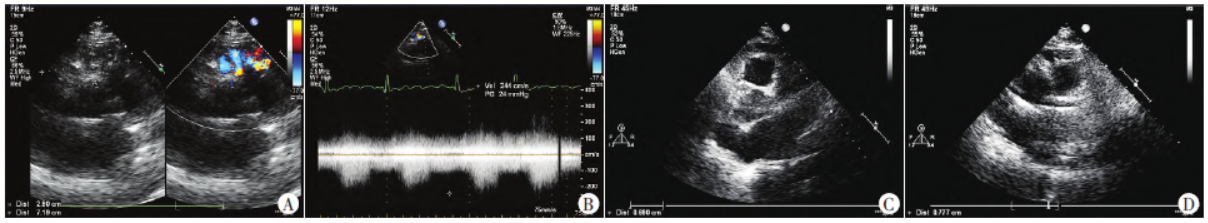

超声心动图提示:左、右冠状动脉扩张伴心底部、大动脉前方血管丛形成(考虑冠状动脉网状血管丛交通形成可能,建议造影检查明确)。冠状动脉血管造影提示:左冠状动脉主干粗大,左冠状动脉前降支-肺动脉瘘(可见巨大血管丛聚集显影并肺动脉管腔显影),中远段显影不清,左冠状动脉回旋支正常;右冠状动脉粗大,右冠状动脉近段-肺动脉瘘(可见巨大血管丛聚集显影并肺动脉管腔显影),中远段管腔完全不显影,见图2。

图2 术前冠状动脉血管造影图。A:左冠状动脉前降支近段粗大,侧支血管增粗、迂曲形成丛样血管团,与造影剂涂染的肿块影相连,远段显影不清;B:右冠状动脉近段主干粗大,侧支血管增粗、迂曲形成丛样血管团,与造影剂涂染的肿块影相连,远段不显影